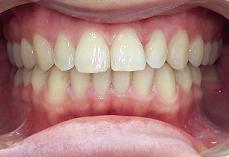

La inspección visual es uno de los pasos básicos en el diagnóstico. Se analizan primeramente parámetros extrabucales como son los tejidos blandos de la cara y articulaciones mandibulares. Seguidamente en el interior de la cavidad bucal, es necesario valorar el aspecto de los tejidos blandos, el estado de las encías y examinar diente por diente. Se prestará especial atención a la relación de contacto entre las dos arcadas dentales.

Dependiendo de cada paciente el diagnóstico necesitará una serie de pruebas y estudios complementarios, como pueden ser radiografías, fotos, o modelos de estudio montados en articulador ( este es un dispositivo que simula los movimientos mandibulares).